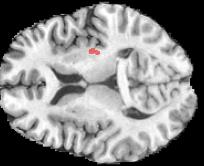

Machine learning models are typically deployed in a test setting that differs from the training setting, potentially leading to decreased model performance because of domain shift. If we could estimate the performance that a pre-trained model would achieve on data from a specific deployment setting, for example a certain clinic, we could judge whether the model could safely be deployed or if its performance degrades unacceptably on the specific data. Existing approaches estimate this based on the confidence of predictions made on unlabeled test data from the deployment's domain. We find existing methods struggle with data that present class imbalance, because the methods used to calibrate confidence do not account for bias induced by class imbalance, consequently failing to estimate class-wise accuracy. Here, we introduce class-wise calibration within the framework of performance estimation for imbalanced datasets. Specifically, we derive class-specific modifications of state-of-the-art confidence-based model evaluation methods including temperature scaling (TS), difference of confidences (DoC), and average thresholded confidence (ATC). We also extend the methods to estimate Dice similarity coefficient (DSC) in image segmentation. We conduct experiments on four tasks and find the proposed modifications consistently improve the estimation accuracy for imbalanced datasets. Our methods improve accuracy estimation by 18\% in classification under natural domain shifts, and double the estimation accuracy on segmentation tasks, when compared with prior methods.